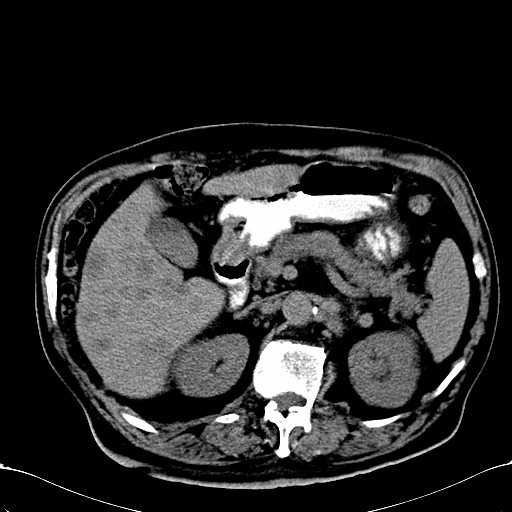

标题: CT28270:胰管扩张,肝多发占位 [打印本页]

标题: CT28270:胰管扩张,肝多发占位

患者,男,75岁。

考虑胰腺钩突癌并肝内转移,建议强化明确。

1)考虑胰头癌并肝脏多发性转移;建议行ct增强扫描检查。2)胃窦癌?建议行胃镜检查。

胰管有扩张,位置比较低,同意楼上几位高手意见。肝内转移可能大,建议增强。

肝脏多方低密度结节,边缘模糊,考虑多发转移,胰管明显扩张,建议增强扫描钩突情况

肝脏多发低密度灶,胰头似呈低密度,胰管扩张,建议增强,

胰管显著扩张,但胆总管未见扩张征象,不太符合胰头占位!考虑慢性胰腺炎.胃窦占位并肝内转移可能!mrcp胃镜增强一起上!